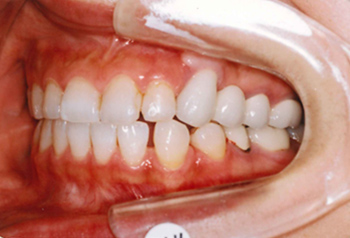

主訴:上顎左側3番を残して欲しい

診断名:上顎左側3番歯肉カリエスにより挺出を行い、上顎左側③4⑤⑥番ブリッジを装着

症状:歯ぎしりがある

患者プロフィール:北九州市小倉北区30代女性

治療方針:上顎左側3番歯肉縁下カリエスにより挺出を行い、上顎左側③4⑤⑥番ブリッジを装着する

治療装置:白い表側矯正装置(マルチブラケット)

抜歯:非抜歯

治療期間:約6か月

説明したリスク副作用:痛み・治療後の後戻り・歯根吸収・歯髄壊死など